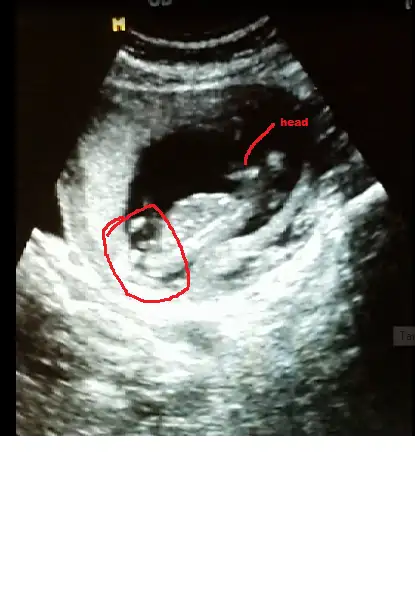

Sagolasin canim yorumun icin ben 13 haftalikken gittigimde ozeldeki doktor yuzde yetmis erkek demisti 2 li icinde devlete gittim soylemedi ondan merak ettim sordum cnm bu arada senin bana msjin gelmedi gelseydi soylerdim cnm

Bebeğin kız canım hayırlı olsun inşallah